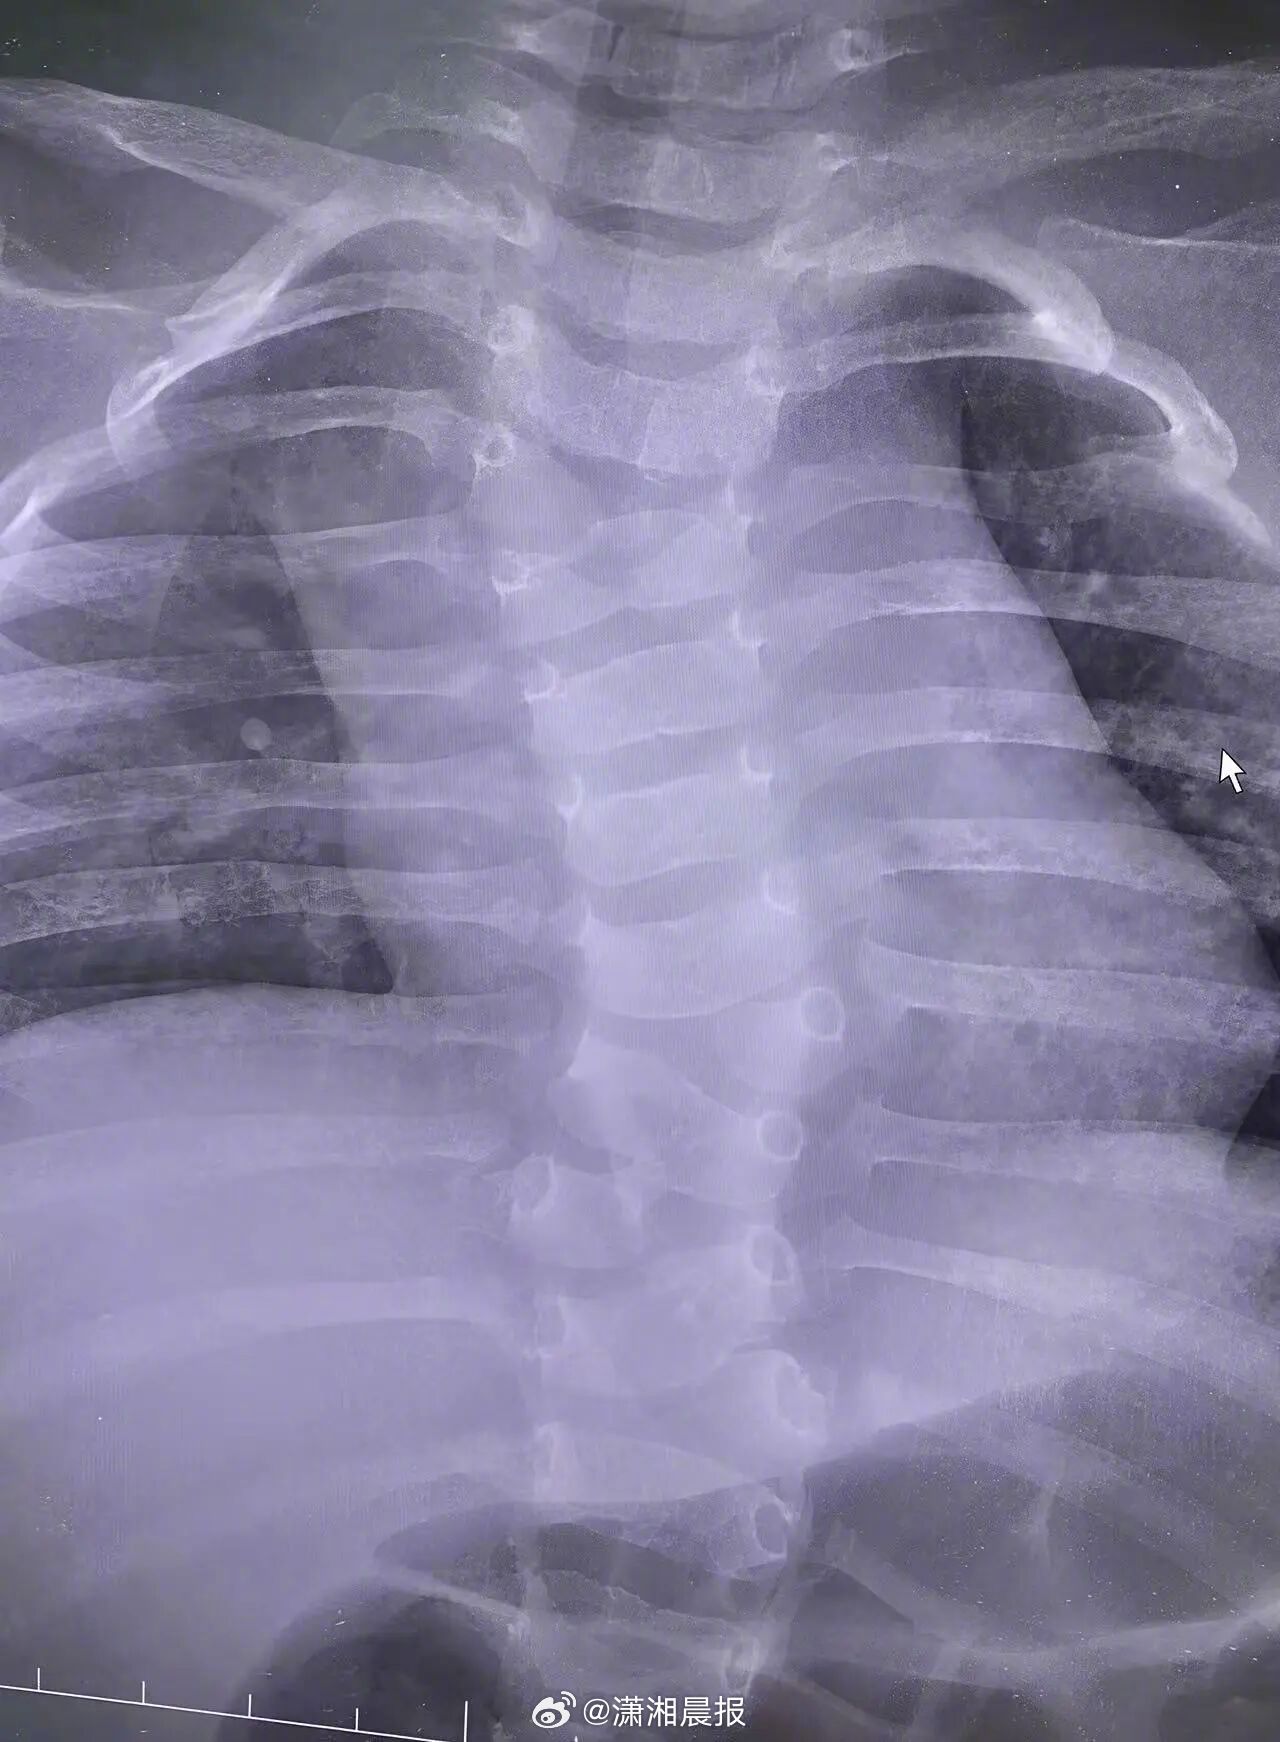

1月13日,张某反映出生幼儿漏诊先天性脊柱畸形医疗问题,黄冈市委市政府高度重视,成立联合调查组,邀请省级相关部门专家,针对张某反映的问题进行全面调查。

调查发现,黄冈市妇幼保健院具备开展产前筛查和产前诊断资质。在本次对张某产前筛查中,医生李某持有《医师执业证》,但未取得《母婴保健技术考核合格证》(产前筛查),未严格按照《中国超声产前筛查指南(2022版)》规范操作,未能获取包含颈胸段的脊柱全段矢状切面图像,调查过程中没有发现人为修改和删减记录;当事医生未能发现疑似缺陷。